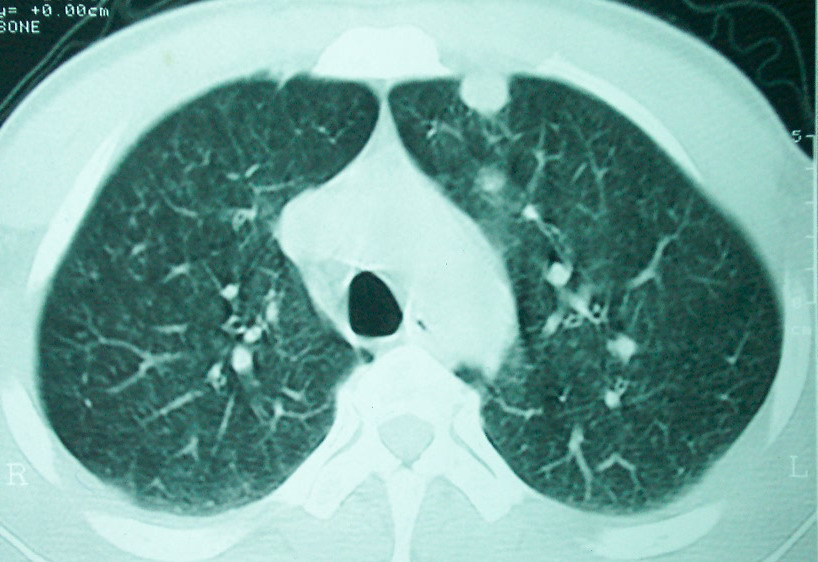

m      37y      发热   咳脓痰月余      ct肺脓肿但住院抗炎治疗后双肺内结节不知该如何解释

治疗后见左肺下野病灶较前缩小但双肺内结节影似无变化请较各位老师该如何下结论    治疗前wbc14.5 治疗后wbc 11.0

血源性肺脓肿,一般由原发感染灶引起脓毒败血症,在肺部形成小脓肿,病变变化快,容易形成肺气囊,脓气胸,主要与转移瘤鉴别,通过临床病史可分

结合临床发热,咳痰考虑为血源性肺脓肿,不过双肺结节又在肺的边缘,还是小心一点,抗炎后复查吧

除了肺内多发结节和左肺下叶的浓疡病灶,还应注意满肺散在的小结节影,还有右上肺前段支气管内膜不光整这些细节,结合病史,肺内多发结节应考虑结核性肉芽!

如果你仔细的同层面对比,你会发现所有的病灶均有比较明显的吸收、缩小。病变的形态,特别是脓肿的形态、壁的厚薄、内壁均有很大的变化,均在往好的方面发展。与临床症状、血像均符合,治疗效果比较显著,就是肺脓肿并双肺的化脓性炎症灶。